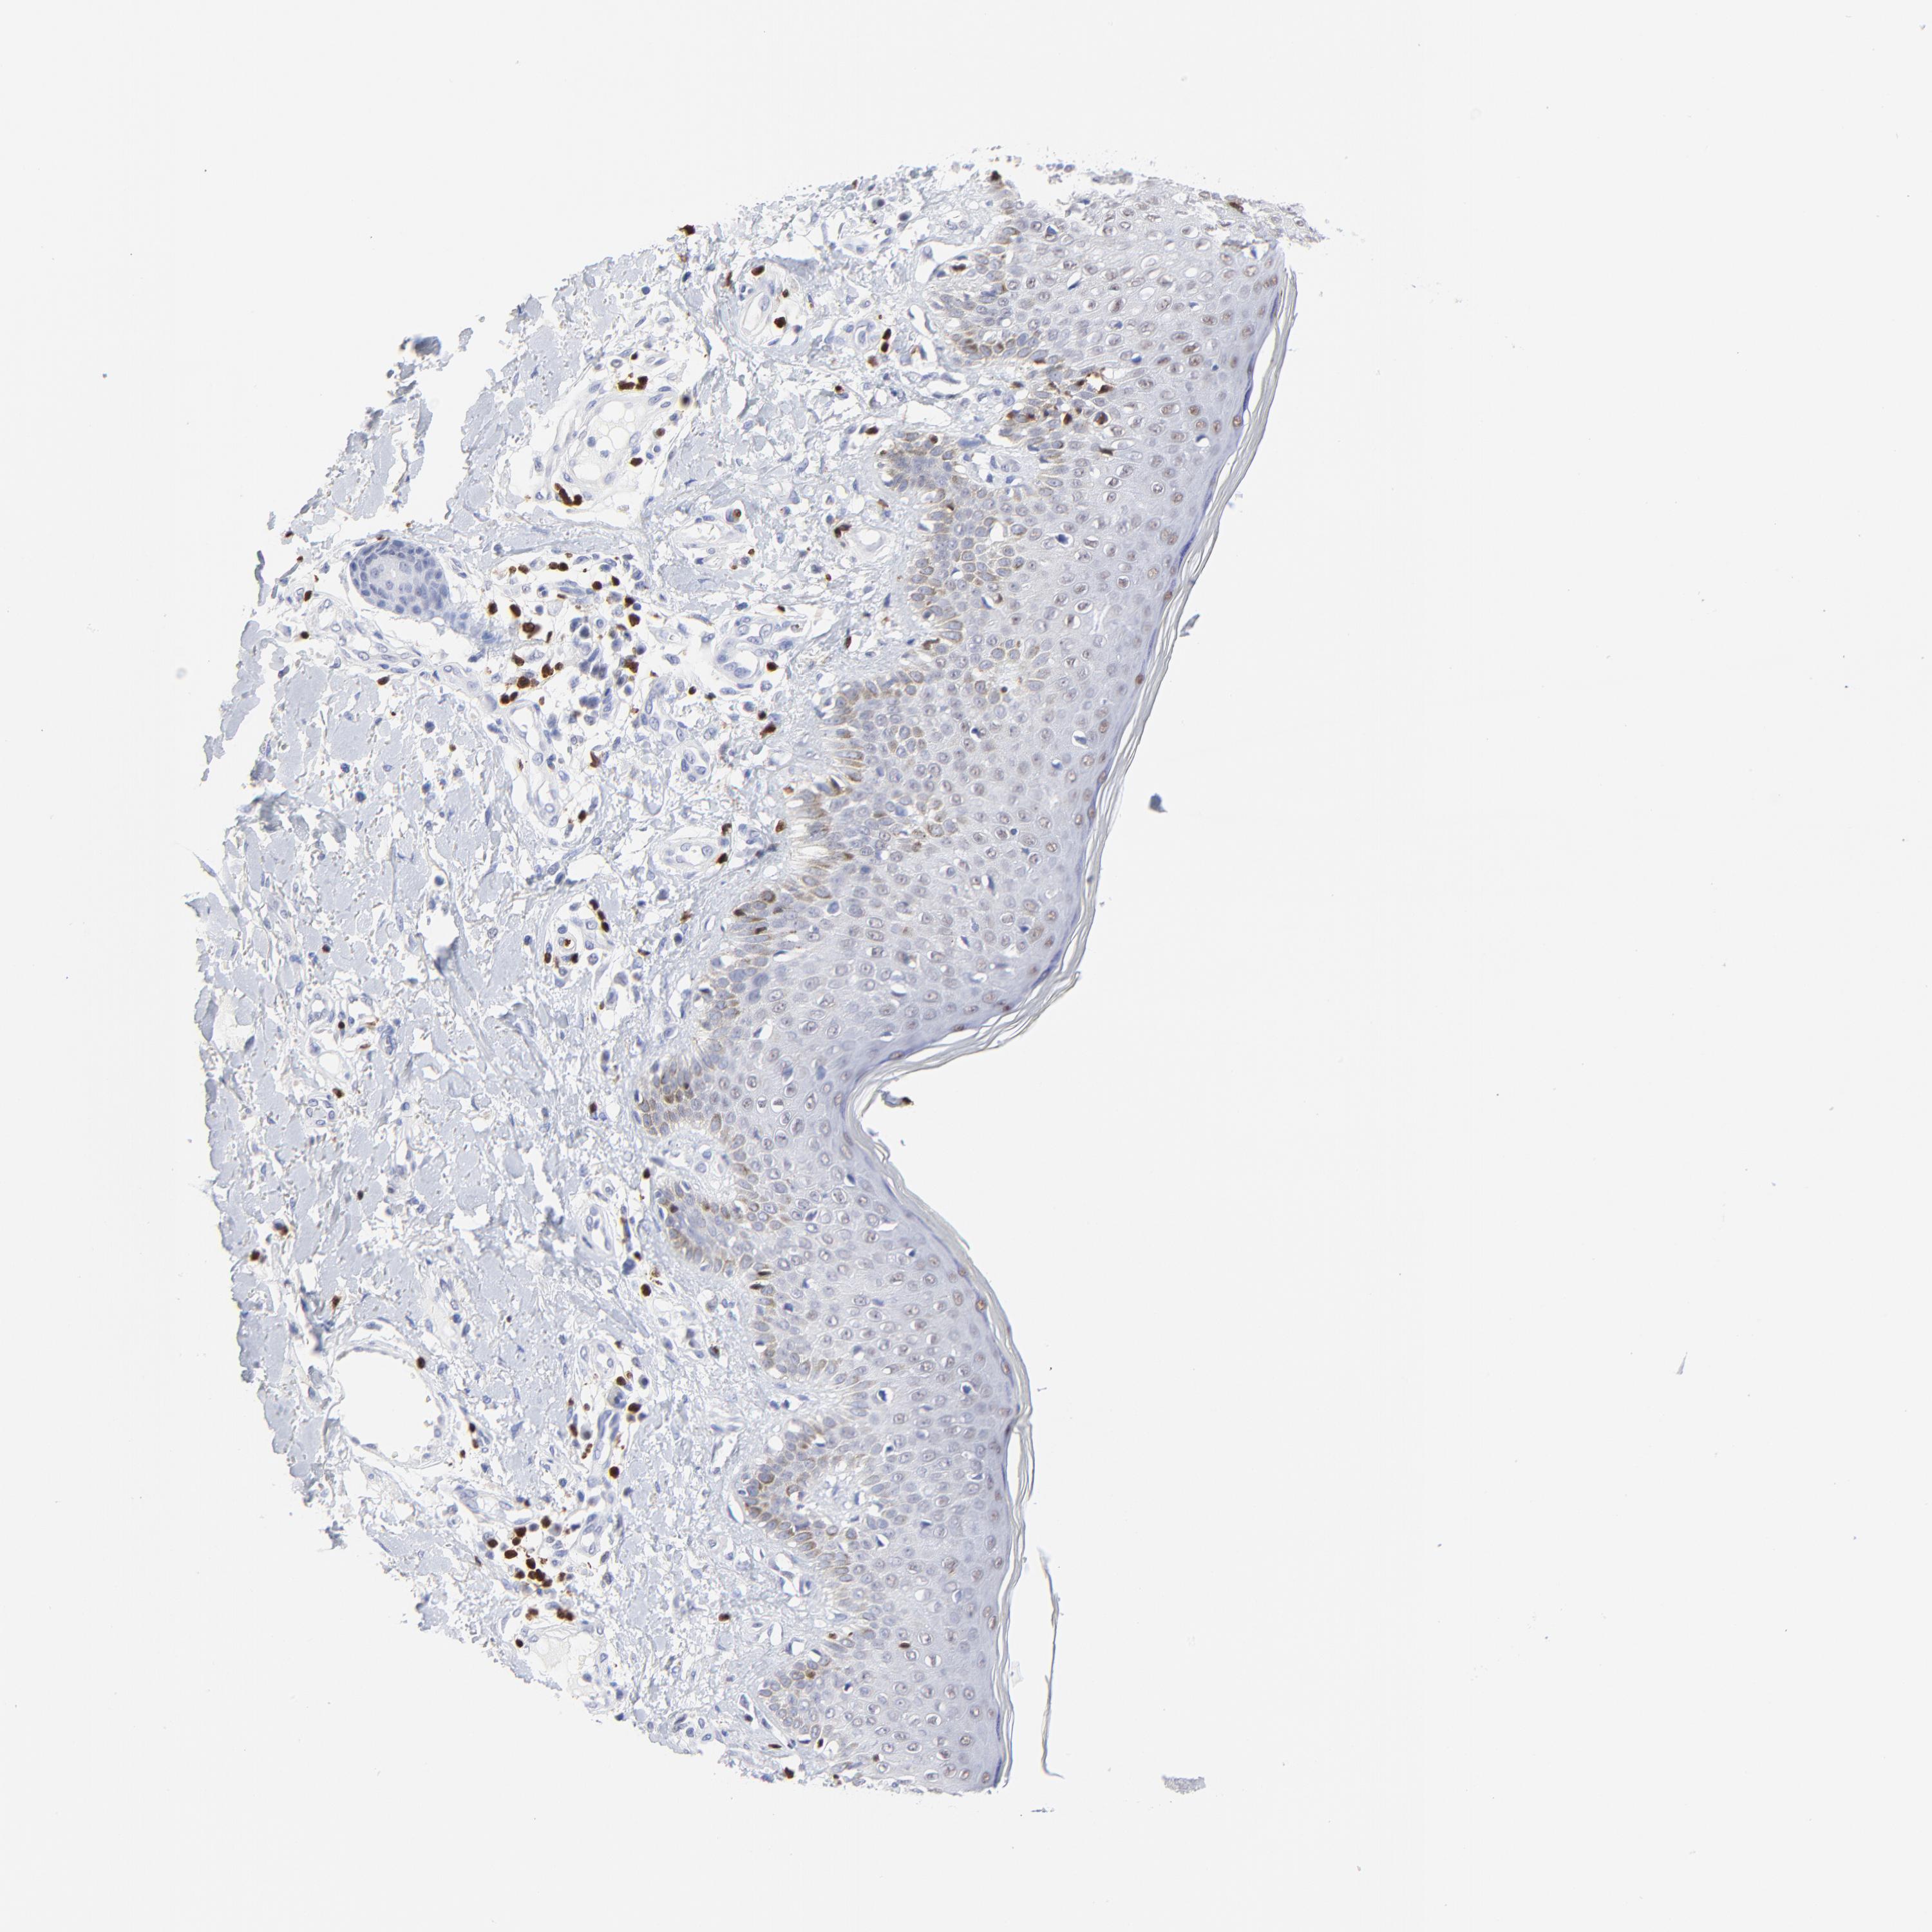

SKIN CANCER - Protein expressioni

A mouse-over function shows sample information and annotation data. Click on an image to view it in a full screen mode. Samples can be filtered based on level of antibody staining by selecting one or several of the following categories: high, medium, low and not detected. The assay and annotation is described here.

Antibody stainingi

Antibody staining in the annotated cell types in the current human tissue is reported as not detected, low, medium, or high, based on conventional immunohistochemistry profiling in selected tissues. This score is based on the combination of the staining intensity and fraction of stained cells.

Each image is clickable and will lead to virtual microscopy that enables deeper exploration of all samples and also displays staining intensity scores, fraction scores and subcellular localization as well as patient and tissue information for each sample.

Antibody HPA003134

Antibody CAB002625

Staining

High

Medium

Low

Not detected

Intensity

Strong

Moderate

Weak

Negative

Quantity

>75%

75%-25%

<25%

None

Location

Nuclear

Cytoplasmic/membranous

Cytoplasmic/membranous,nuclear

Squamous cell carcinoma, NOS

Basal cell carcinoma